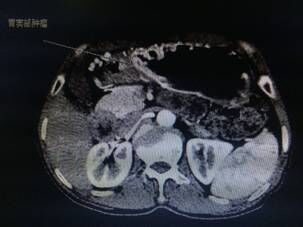

我院胃腸外科今年3月收治一名男性患者,以反復腹痛7月入院,CT提示胃竇部及乙狀結(jié)腸占位性病變(分別見圖1、2),行內(nèi)窺鏡活檢分別考慮胃腺癌以及乙狀結(jié)腸絨毛狀腺瘤,不排除惡變傾向。為改善患者生存率,減少創(chuàng)傷,手術(shù)團隊決定充分發(fā)揮腹腔鏡技術(shù)優(yōu)勢,采用腹腔鏡下一期同時切除胃、結(jié)腸病變,由于患者乙狀結(jié)腸病變惡性診斷不明確,根據(jù)腫瘤根治的原則,先處理乙狀結(jié)腸。手術(shù)當中依據(jù)冰凍切片,在腹腔鏡下首先完成乙狀結(jié)腸癌根治,后行腹腔鏡下遠端胃癌根治術(shù)。一次微創(chuàng)手術(shù),切除兩個腫瘤,免除了患者傳統(tǒng)剖腹手術(shù)及二次手術(shù)的創(chuàng)傷,縮短了住院時間,術(shù)后恢復快,降低了患者住院費用。

圖片1                               圖片2